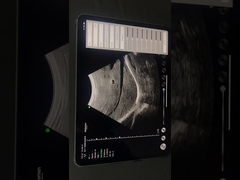

Calidad Escáner de ultrasonido portátil, analizador del ultrasonido del PDA Fabricante de China

Ultrasound scanner